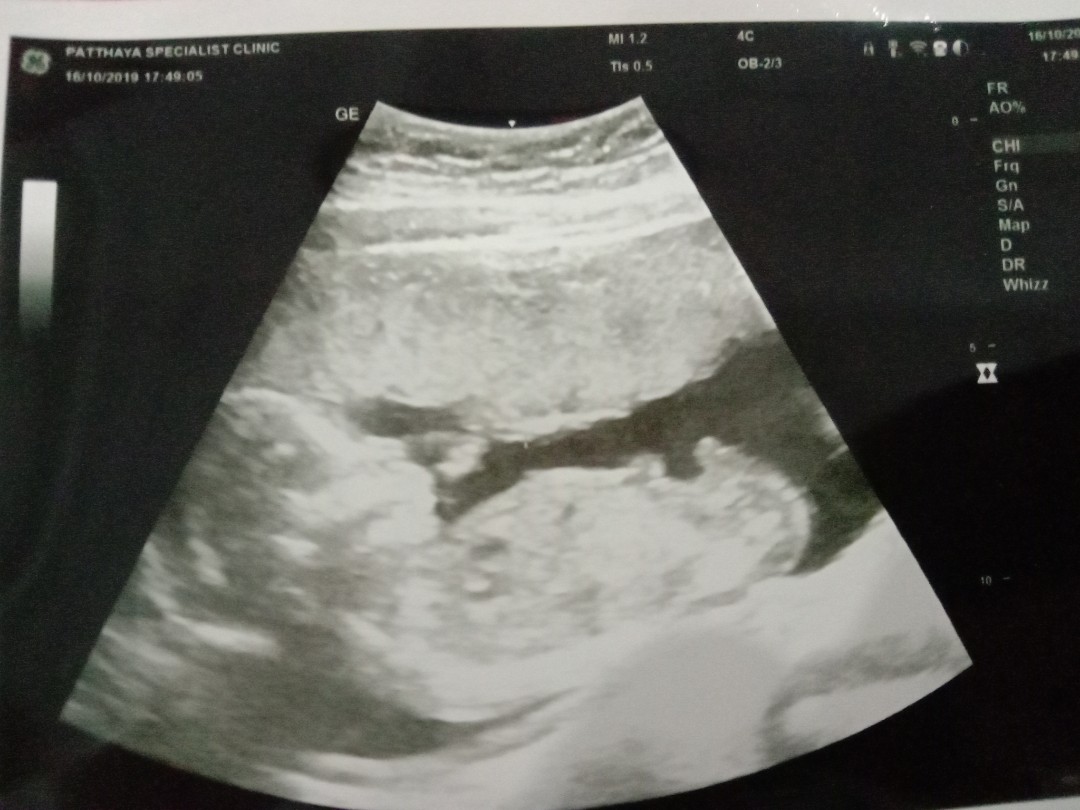

กำหนดคลอดเดือนมีนา63

บ้านไหนกำหนดคลอดเดือนมีนาคม63บ้างค่ะ บ้านนี้10มีนาคม63 ยังไม่รู้เพศ หมอไม่ดูเพศให้ค่ะ